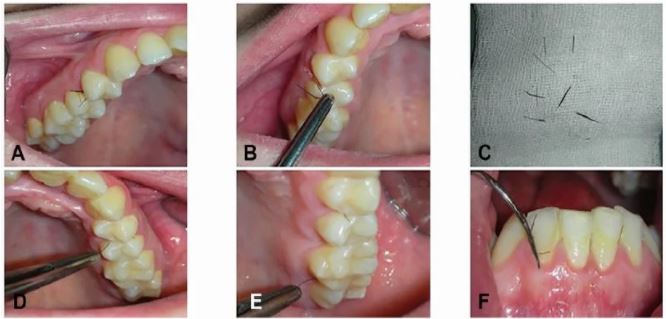

في حين أن متلازمة تكيس المبايض قد لا تكون سببًا ، فمن شبه المؤكد أنها أدت إلى تفاقم الوضع، ورغم إزالة الشعر جراحيا وعودة المريضة لحياة خالية من نمو الشعر في أماكن غريبة، استمرت لفترة بدون تناول الأدوية، وهذه المرة لم يقم الفريق الطبي بإزالة الشعر فقط، وأخذوا جزء صغير من الأنسجة لإلقاء نظرة تحت المجهر، ووجدوا الشعر يخرج بشكل غريب عبر أنسجة اللثة.